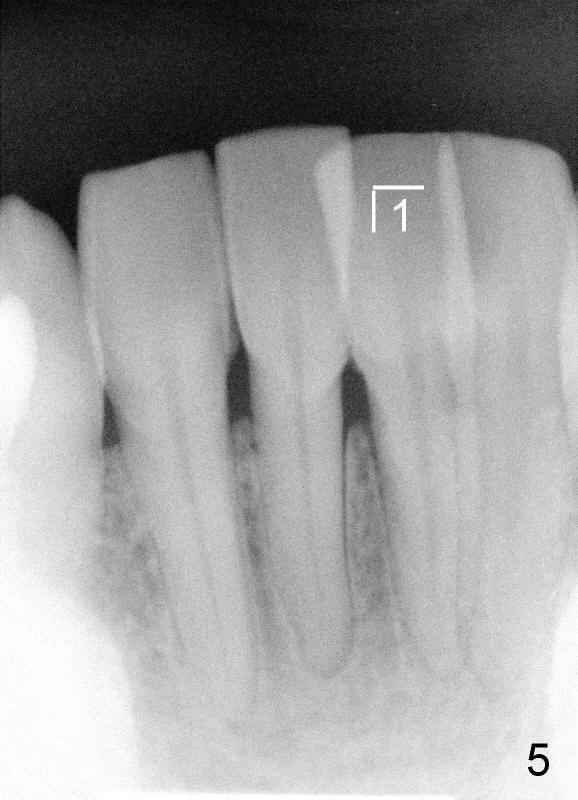

Forty-year-old man had ortho with extraction in his teens (Fig.1,2: B: bicuspid). Without wearing retainers, relapse occurs, particularly in the lower anterior. The lower left central incisor shifts labially with gingival recession (Fig.2,3). The attached gingiva is narrow for this incisor as compared to that of the neighboring tooth (Fig.4 between arrowheads). Although there is abundance of calculus, bone loss is mild to moderate (Fig.5-7). Scaling and root planing was finished today with schedule of perio maintenance every 3 months.

Both arches are narrow (Fig.1,2). Will be there space to move the lower left central lingually? Once the tooth is in normal position, gingival graft is performed to correct recession.